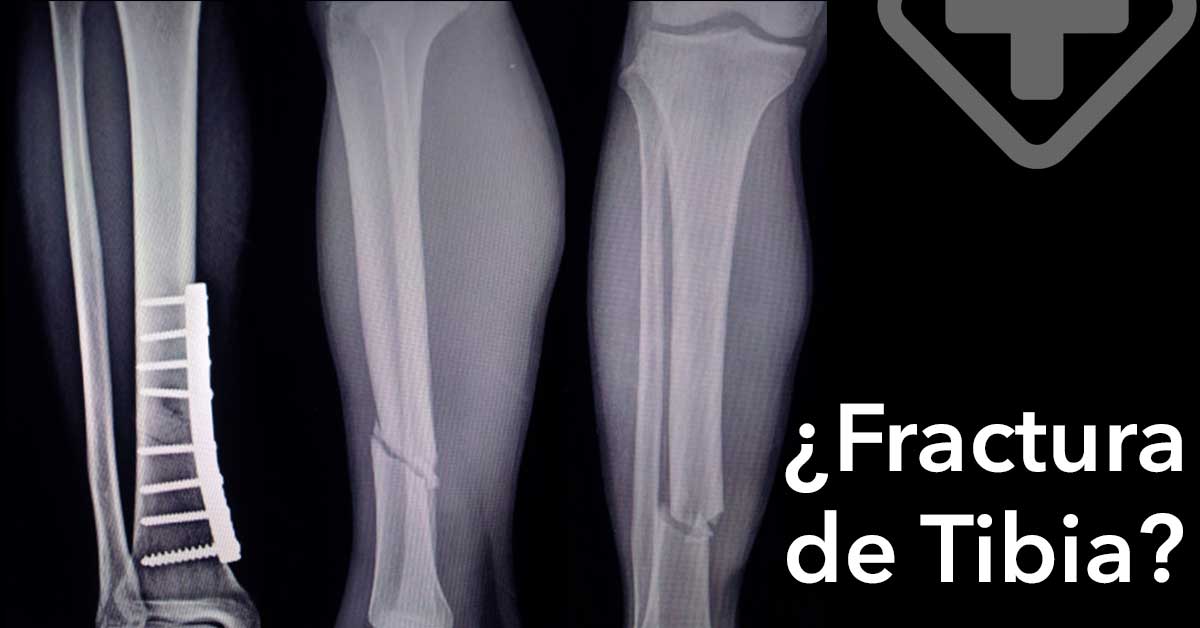

Para diagnosticar una fractura de tibia, el médico preguntará sobre tu historial médico y cómo ocurrió la lesión. Llevará a cabo una examinación y pedirá realizar alguna de las siguientes pruebas:

En casos severos, la cirugía puede ser necesaria para asegurar que el hueso sane correctamente. El Cirujano Ortopedista o Traumatólogo puede recurrir a placas y tornillos metálicos para fijar el hueso en su lugar, permitiendo la óptima recuperación del hueso con daño mínimo en el largo plazo. Este procedimiento es conocido como osteosíntesis.

El Cirujano Ortopedista o Traumatólogo puede también utilizar varillas o clavos metálicos para colocarlos a través de los huesos, por encima y debajo de la fractura. Estos se unirán a un marco rígido llamado fijador externo, y mantendrán el hueso en su lugar.